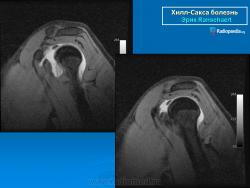

На рентгенограмме плечевого сустава определяется умеренный остеопороз головки плечевой кости. Иногда на ее задненаружной поверхности позади вершины большого бугорка выявляется вдавленный дефект (повреждение Хилл-Сакса). Дефект четко виден на рентгенограмме в аксиальной проекции. Аналогичный, но менее выраженный дефект может быть выявлен в зоне передненаружного края суставной впадины лопатки. Также в диагностике причин привычного вывиха плеча помогает МРТ исследование.